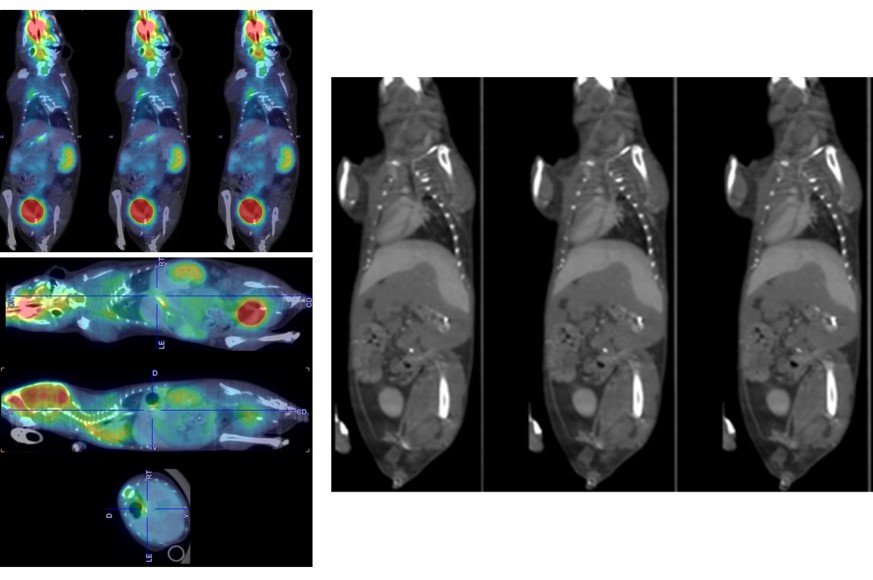

FDG/PET-CT Multi-Mouse

Brain & Body

Multi-Animal Dynamic 18FDG-PET/CT in a Mouse Tumor Model

Dynamic PET with low dose injection: 3 MBq 18FDG